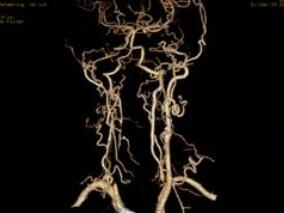

女66岁,言语不能、四肢活动不灵6天,加重1天

1小时条评论女,66岁,右利手。 主诉:言语不能、四肢活动不灵6天,加重1天。 病史:患者6天前晨起活动中出现头晕、言语困难、四肢活动不灵,可少量进食,无明显呛咳,时而糊涂,强哭,不识家人,伴尿失禁。行头颅CT检查:双侧脑室旁、基底节及脑桥小片低密度影(与2月前头颅C...